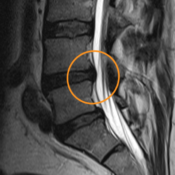

Hérnias Discais – Tratamento

Hérnia Discal A dor lombar ou “dor de costas” é um dos sintomas com maior prevalência na população. Estima-se que cerca de 80% da população mundial, pelo menos uma vez na vida, apresente queixas de dores relacionadas com a coluna. Por vezes, é suficientemente intensa e incapacitante, com importante interferência na capacidade de trabalho e […]